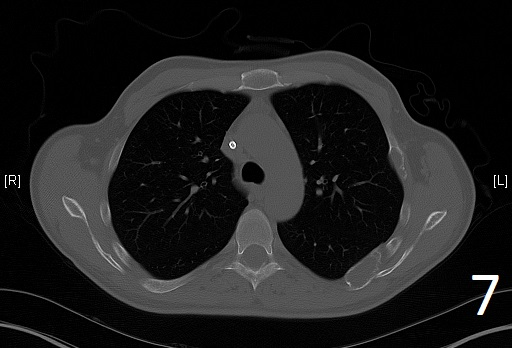

Fig. 7

Fig. 6-7. Axial CT reconstruction of the chest showing lytic and expansile lesion of the left scapula and ribs (polyostotic fibrous dysplasia).